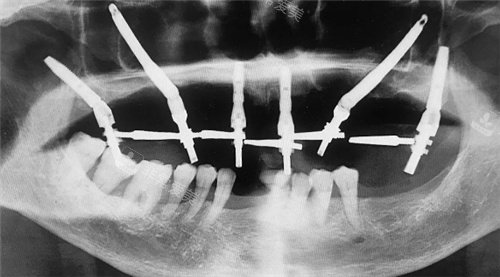

穿颧穿翼图示